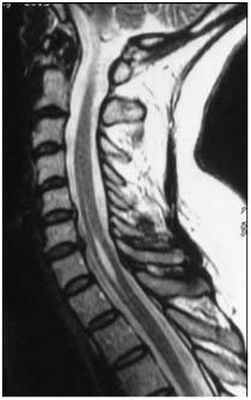

2. Посттравматическая сирингомиелия. Как правило, сирингомиелическая киста возникает в месте повреждения, а затем распространяется на другие сегменты спинного мозга. Симптомы могут появляться через несколько месяцев или лет после заболевания, когда пациент считает себя уже «выздоровевшим».

МРТ изображение (T1-взвешенное изображение) пациента с тяжелым повреждением спинного мозга и шейного отдела позвоночника (С7) в результате «травмы ныряльщика». Обратите внимание на полость (темная полоска в середине спинного мозга), которая простирается кверху и книзу от уровня повреждения. Сразу после травмы у пациента развилась слабость в ногах, а впоследствии возникла слабость в руках из-за сирингомиелии.